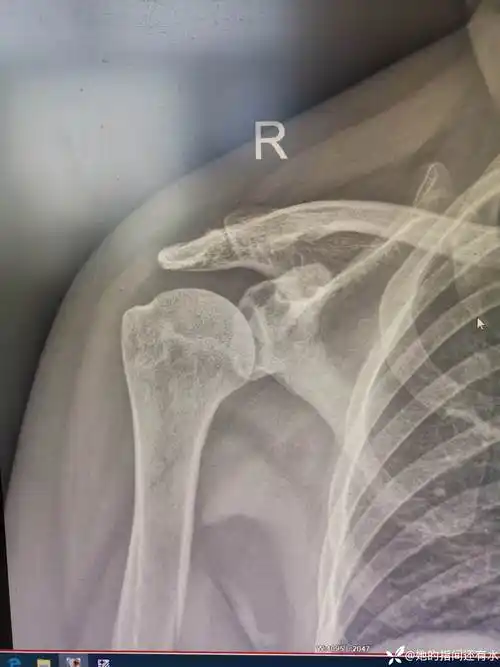

中年女性,发现右肩关节占位2天.有特征,有细节---(有结果)

陈旧性肩锁关节脱位